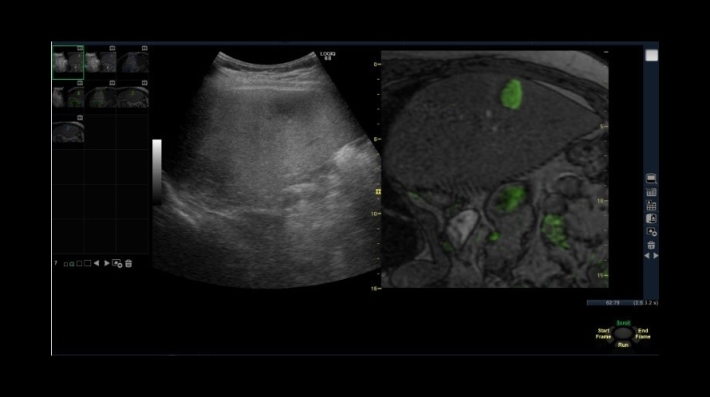

• Contrast Option Package — режим кодированной контрастной гармоники для проведения исследований с контрастными веществами;

• Parametric Contrast Imaging Option — опция параметрического контрастного изображения;

• HiRES Contrast Imaging Upgrade — опция контрастного изображения высокого разрешения;

• Функция контрастной эхографии увеличивает глубину проникновения луча и повышает его чувствительность;